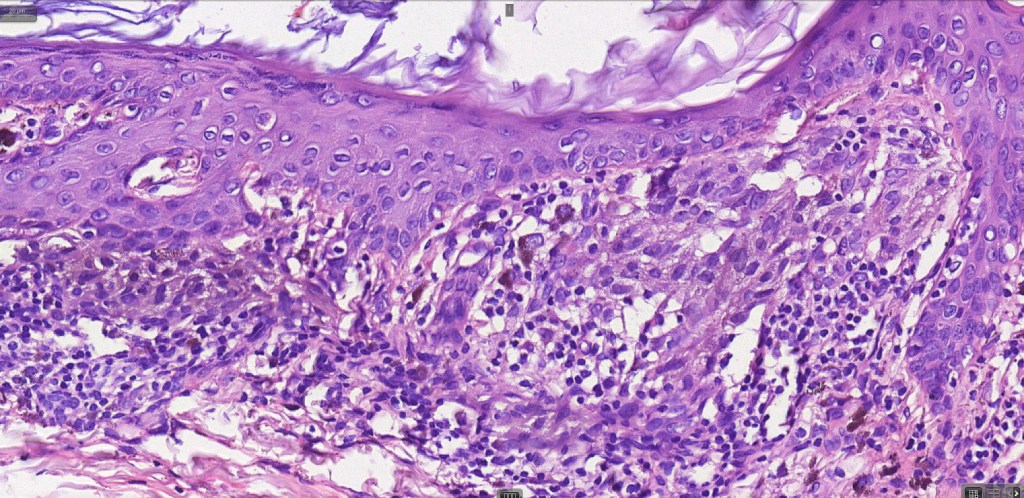

•Large dyscohesive nests with retraction artifact, not restricted to the tips of the epidermal ridges

•Bridging common, often over multiple rete ridges

•Variable atypia (can be marked)

•Superficial dermal atypia

•Junctional mitoses sometimes present, dermal mitoses+/-, can be multiple but never atypical

•Dermal fibrosis (sometimes lamellar)